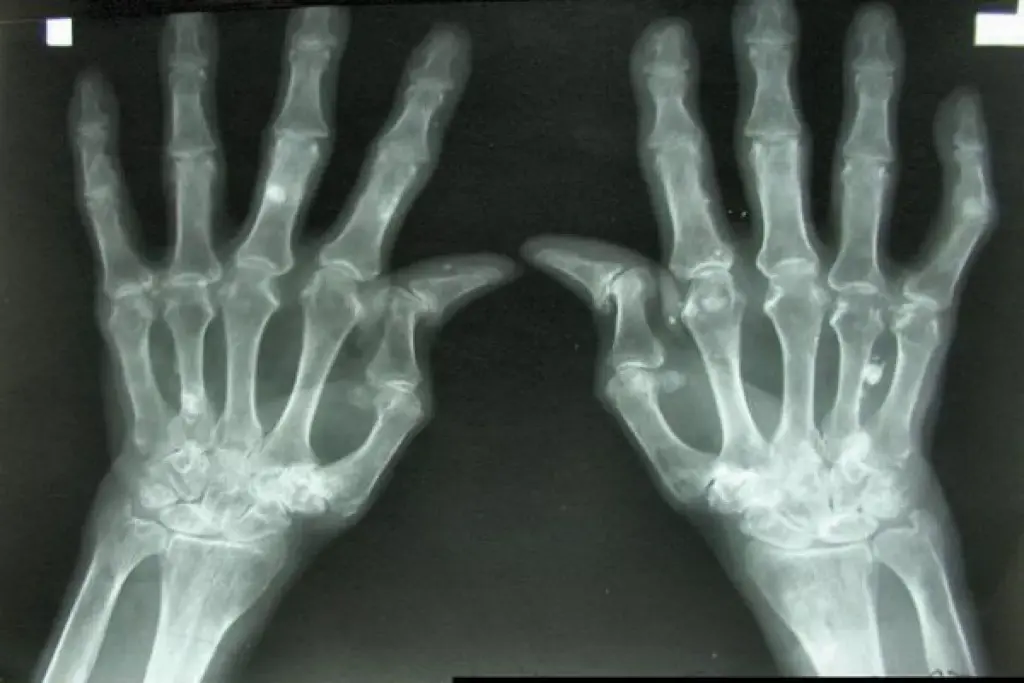

High RF levels mean the disease is getting worse. They also raise the risk of rheumatoid nodules and lung problems. Research shows that higher RF levels are linked to a poorer prognosis in rheumatoid arthritis. This highlights the importance of a detailed approach to diagnosis and treatment.

High RF levels may correlate with more aggressive disease, increased joint damage, and higher risk of complications.